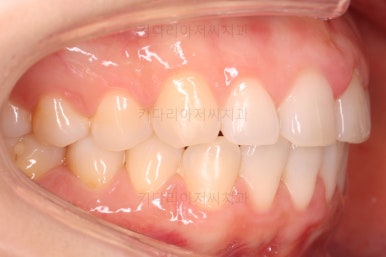

어금니쪽의 맞물림은 굉장히 양호한 편이였기 때문에 부분교정에 딱 알맞는 경우였어요.

왼쪽 사진들이 부산나비앞니교정 치료 전 모습, 오른쪽 사진들이 치료 후의 모습입니다.

가지런해진 느낌이 전후 비교해보니 훨씬 느껴지실 거에요.